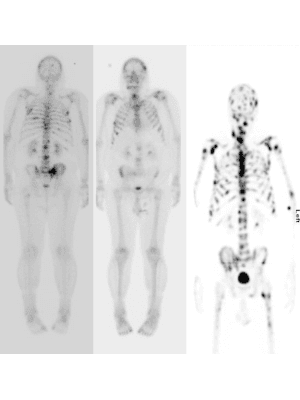

Nuclear medicine imaging has always played an important role in the management of patients with prostate cancer, both pre and post therapy. This has primarily been through the use of conventional gamma camera imaging and bone scans for the detection of metastatic bone disease for which prostate cancer has a predilection. The role of nuclear medicine has seen recent, rapid evolution and expansion in this patient group, both because of enhanced imaging techniques for these conventional bone tracers which improve sensitivity and specificity (eg whole body single photon emission computed tomography [SPECT] and SPECT/CT) and, more recently, by the development and burgeoning availability of PET tracers.